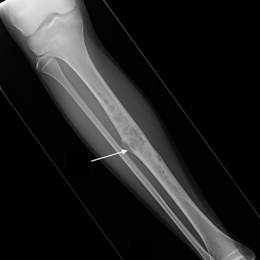

Radiographic imaging is used to help form a diagnosis of ABC. These include X-Ray, MRI, CT and Bone Scans

An example of an Adamantinoma X-Ray is shown.

98A) Plain AP X Ray Of Right Tibia Adamantinoma